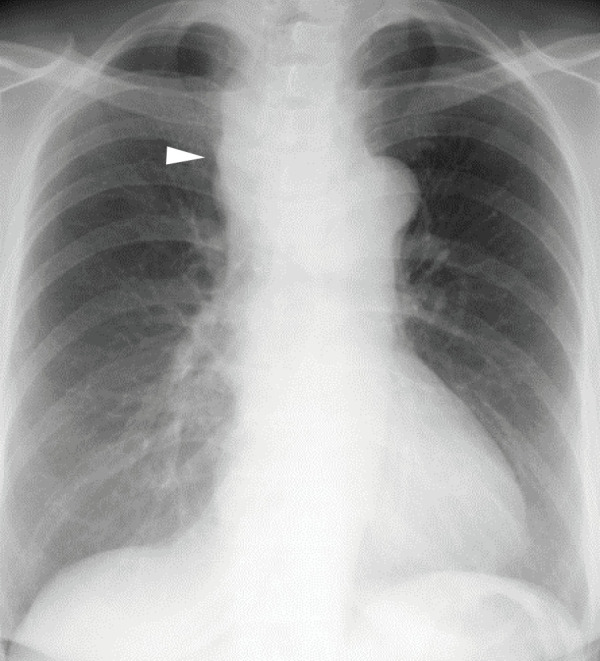

Case presentation: A 64-year-old woman with exertional dyspnea was diagnosed with a superior mediastinal cyst compressing the trachea and esophagus. Preoperative EUS-FNA was performed to reduce the cyst volume and any mitigate potential complications during anesthesia induction. Three days later, she developed dyspnea due to a delayed intracystic hemorrhage, necessitating emergency surgery. VATS with a confronting upside-down monitor setup was performed under standby V-A ECMO. Despite a limited surgical field under 2-lung ventilation, a confronting upside-down VATS approach allowed sufficient visualization and maneuverability. The patient had an uneventful recovery, with no recurrence at 3 months.